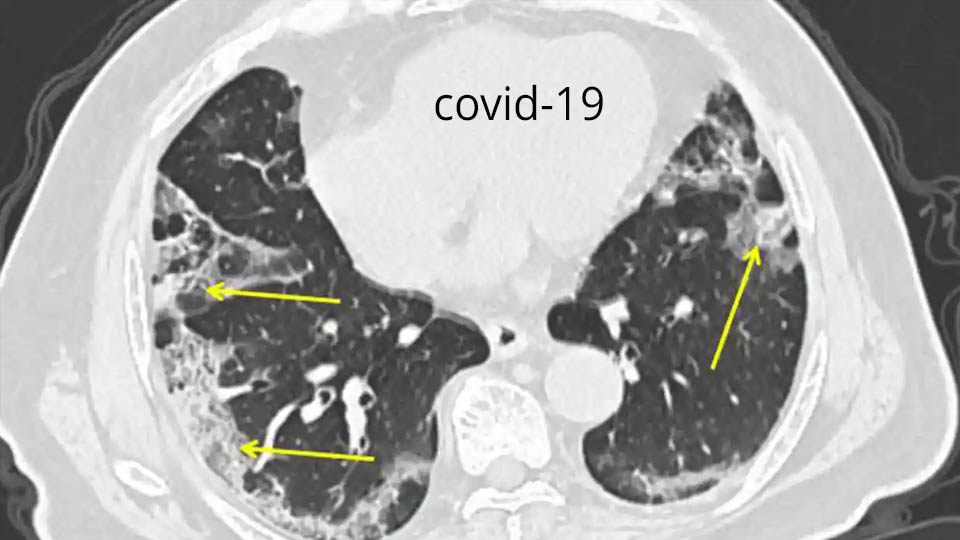

កូវីដ-១៩ ៖ តើជំងឺរលាកសួតកើតឡើងយ៉ាងដូចម្តេច?

កូវីដ-១៩ និងជំងឺរលាកសួត